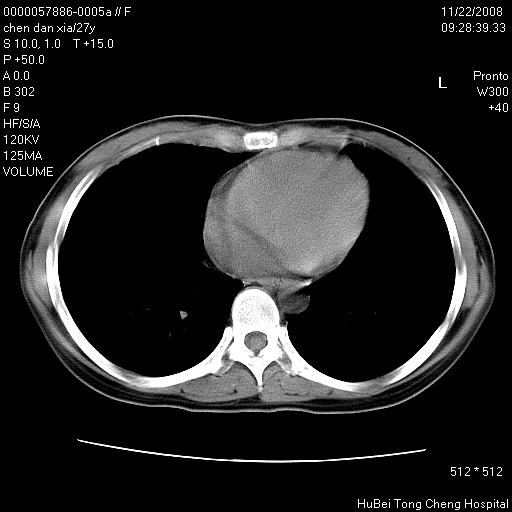

标题: CT16752:F,27Y。发热咳嗽20余天,伴盗汗。 [打印本页]

标题: CT16752:F,27Y。发热咳嗽20余天,伴盗汗。

右下肺见片絮状影,两肺野内分布不均的小结节影,结核并肺内播散可能性大,建议结合实验室检查 .

右下肺纹理模糊;纵隔可见肿大淋巴节;右心缘旁结节,边缘光滑,纵隔窗病变范围较肺窗明显小,首先考虑右下肺结核,不排外淋巴瘤

双肺纹影普多,部分呈网状,支炎或淋巴管炎?

纵隔内淋结肿

局部胸膜增厚

似有粟米状结节。考虑粟粒型肺结核?